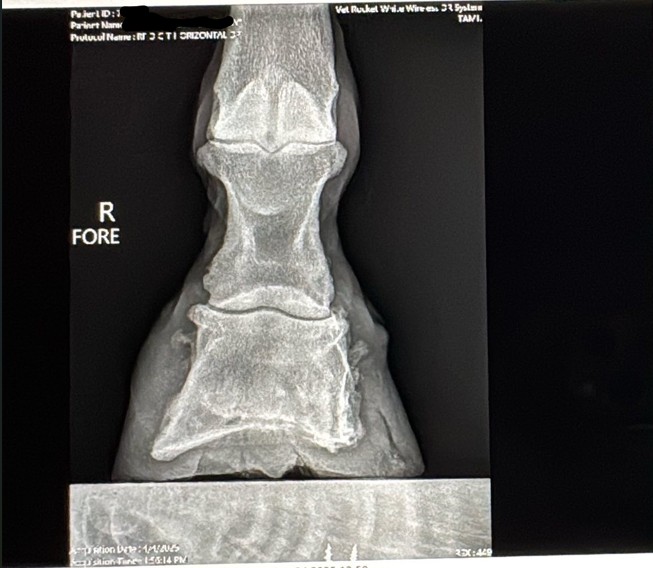

Rennie, a 2016 AQH, is a medical mystery; by all means, he shouldn't be standing, running, or jumping around the paddock. He was rescued in 2023 by a small family who help horses, skin and bones with a severe and constant limp in his right foreleg. We got him in February 2024, a great weight, but he still had a mysterious lameness that we couldn't figure out. After research, I found scoot boots. They took him from constant 3-4/5 lameness to a 1-2 lameness. Sound to be ridden (although he is just a paddock pet) We took x-ray at Texas A&M, the whole team was shocked, wondering how he is still alive with full fusion of his coffin, navicular and P3. His not only walking, but he is sound, happy, and a loving liberty pony. He came from a background of severe abuse. He has the physical and emotional scars of control-based training methods that left deep trauma: rope burns, whip marks, slashed legs, and twisted ears told a story of cruelty I wouldn’t wish on any animal. He had spent his final months before rescue in the auction pipeline.

I turned back to Rennie’s old farrier, the only one he and I trusted, but his flare-ups worsened, and without clear x-rays, we had little understanding of what was truly happening inside his hoof. I consulted my vet about quality of life, corrective shoeing, and every option we had left. When Texas A&M provided new x-rays, the truth was undeniable. His fusion was so severe that most professionals believed there was no choice but euthanasia. One corrective shoer refused to even see him, stating simply, "The horse should be put down."

But the team at Texas A&M saw what I saw—Rennie was defying the odds. Corrective shoeing wasn’t the answer. Traditional shoes would only add more stress, but Scoot Boots gave him freedom. They allowed his hoof to move as naturally as possible, relieving pressure without restricting movement. The specialists were amazed—not just at his ability to move, but at how much the boots had helped him. Without them, he wouldn’t be sound. Without them, I would have had to make the hardest decision.